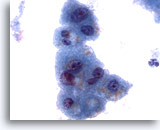

画像 3

肝FNA – 良性肝細胞

核はわずかに大小不同であり、反応性変化を来した肝細胞に典型的な低N/C比を示します。微小な細胞質空胞および細胞質内色素がみられます。

60倍

画像 3

肝FNA – 良性肝細胞

核はわずかに大小不同であり、反応性変化を来した肝細胞に典型的な低N/C比を示します。微小な細胞質空胞および細胞質内色素がみられます。

60倍